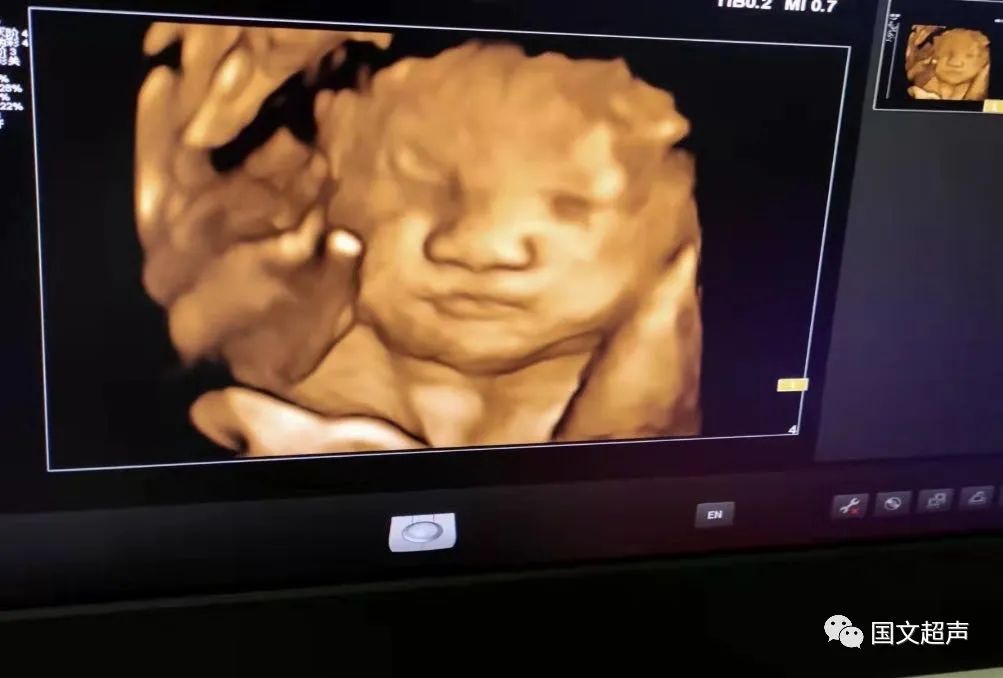

一.飛利浦EPIQ7高端四維彩超

我院目前使用的是飛利浦EPIQ7高端四維彩超,它擁有高品質(zhì)自動成像分析技術(shù),分辨率及清晰度高,可以較清晰的顯示宮內(nèi)胎兒的生長發(fā)育情況,為診斷胎兒先天性畸形,如唇裂、脊柱裂、顱腦發(fā)育異常、骨骼發(fā)育異常、心血管畸形等提供準(zhǔn)確的科學(xué)依據(jù)。